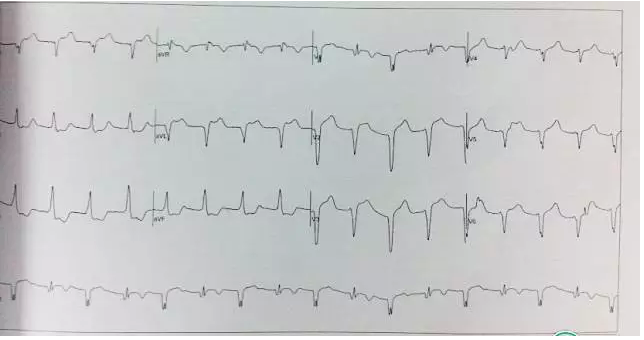

入院心电图: 7月4日:内分泌科,普通ECG,正常。

运动平板:ST段压低。